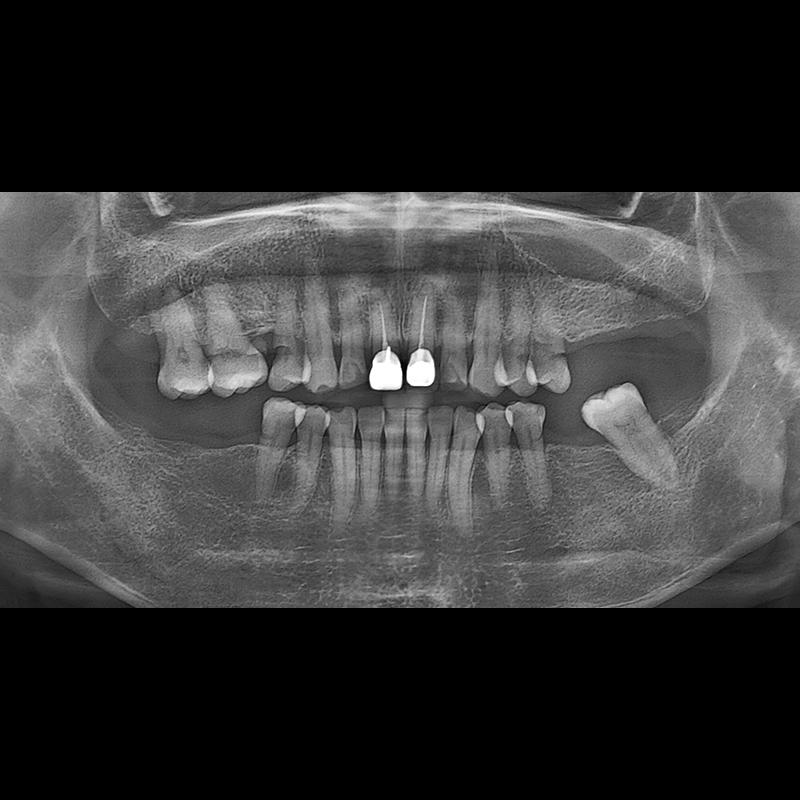

BEFORE AFTER

种植牙前后的照片 2025.05.30

在缺失的牙齿部分和难以挽救的牙齿位置植入了种植牙。